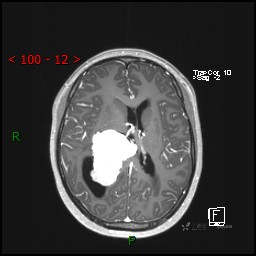

视物模糊发现颅内占位,“豆蔻年华”却承受开颅之痛,所幸一切顺利---结果公布~

患者年龄:14岁

简要病史:患者于1月前无明显诱因出现视物模糊,无明显头痛头晕,无恶心呕吐,无昏迷,无肢体偏瘫等症状,就诊于当地医院头部CT考虑:右侧丘脑、脑室占位。予以对症处置后家属为求进一步诊治来我科,以“颅内占位”收入院。 起病以来,精神、饮食、睡眠欠佳,大小便正常,体力下降,体重无明显变化。

临床诊断:脑室占位

MRI平扫